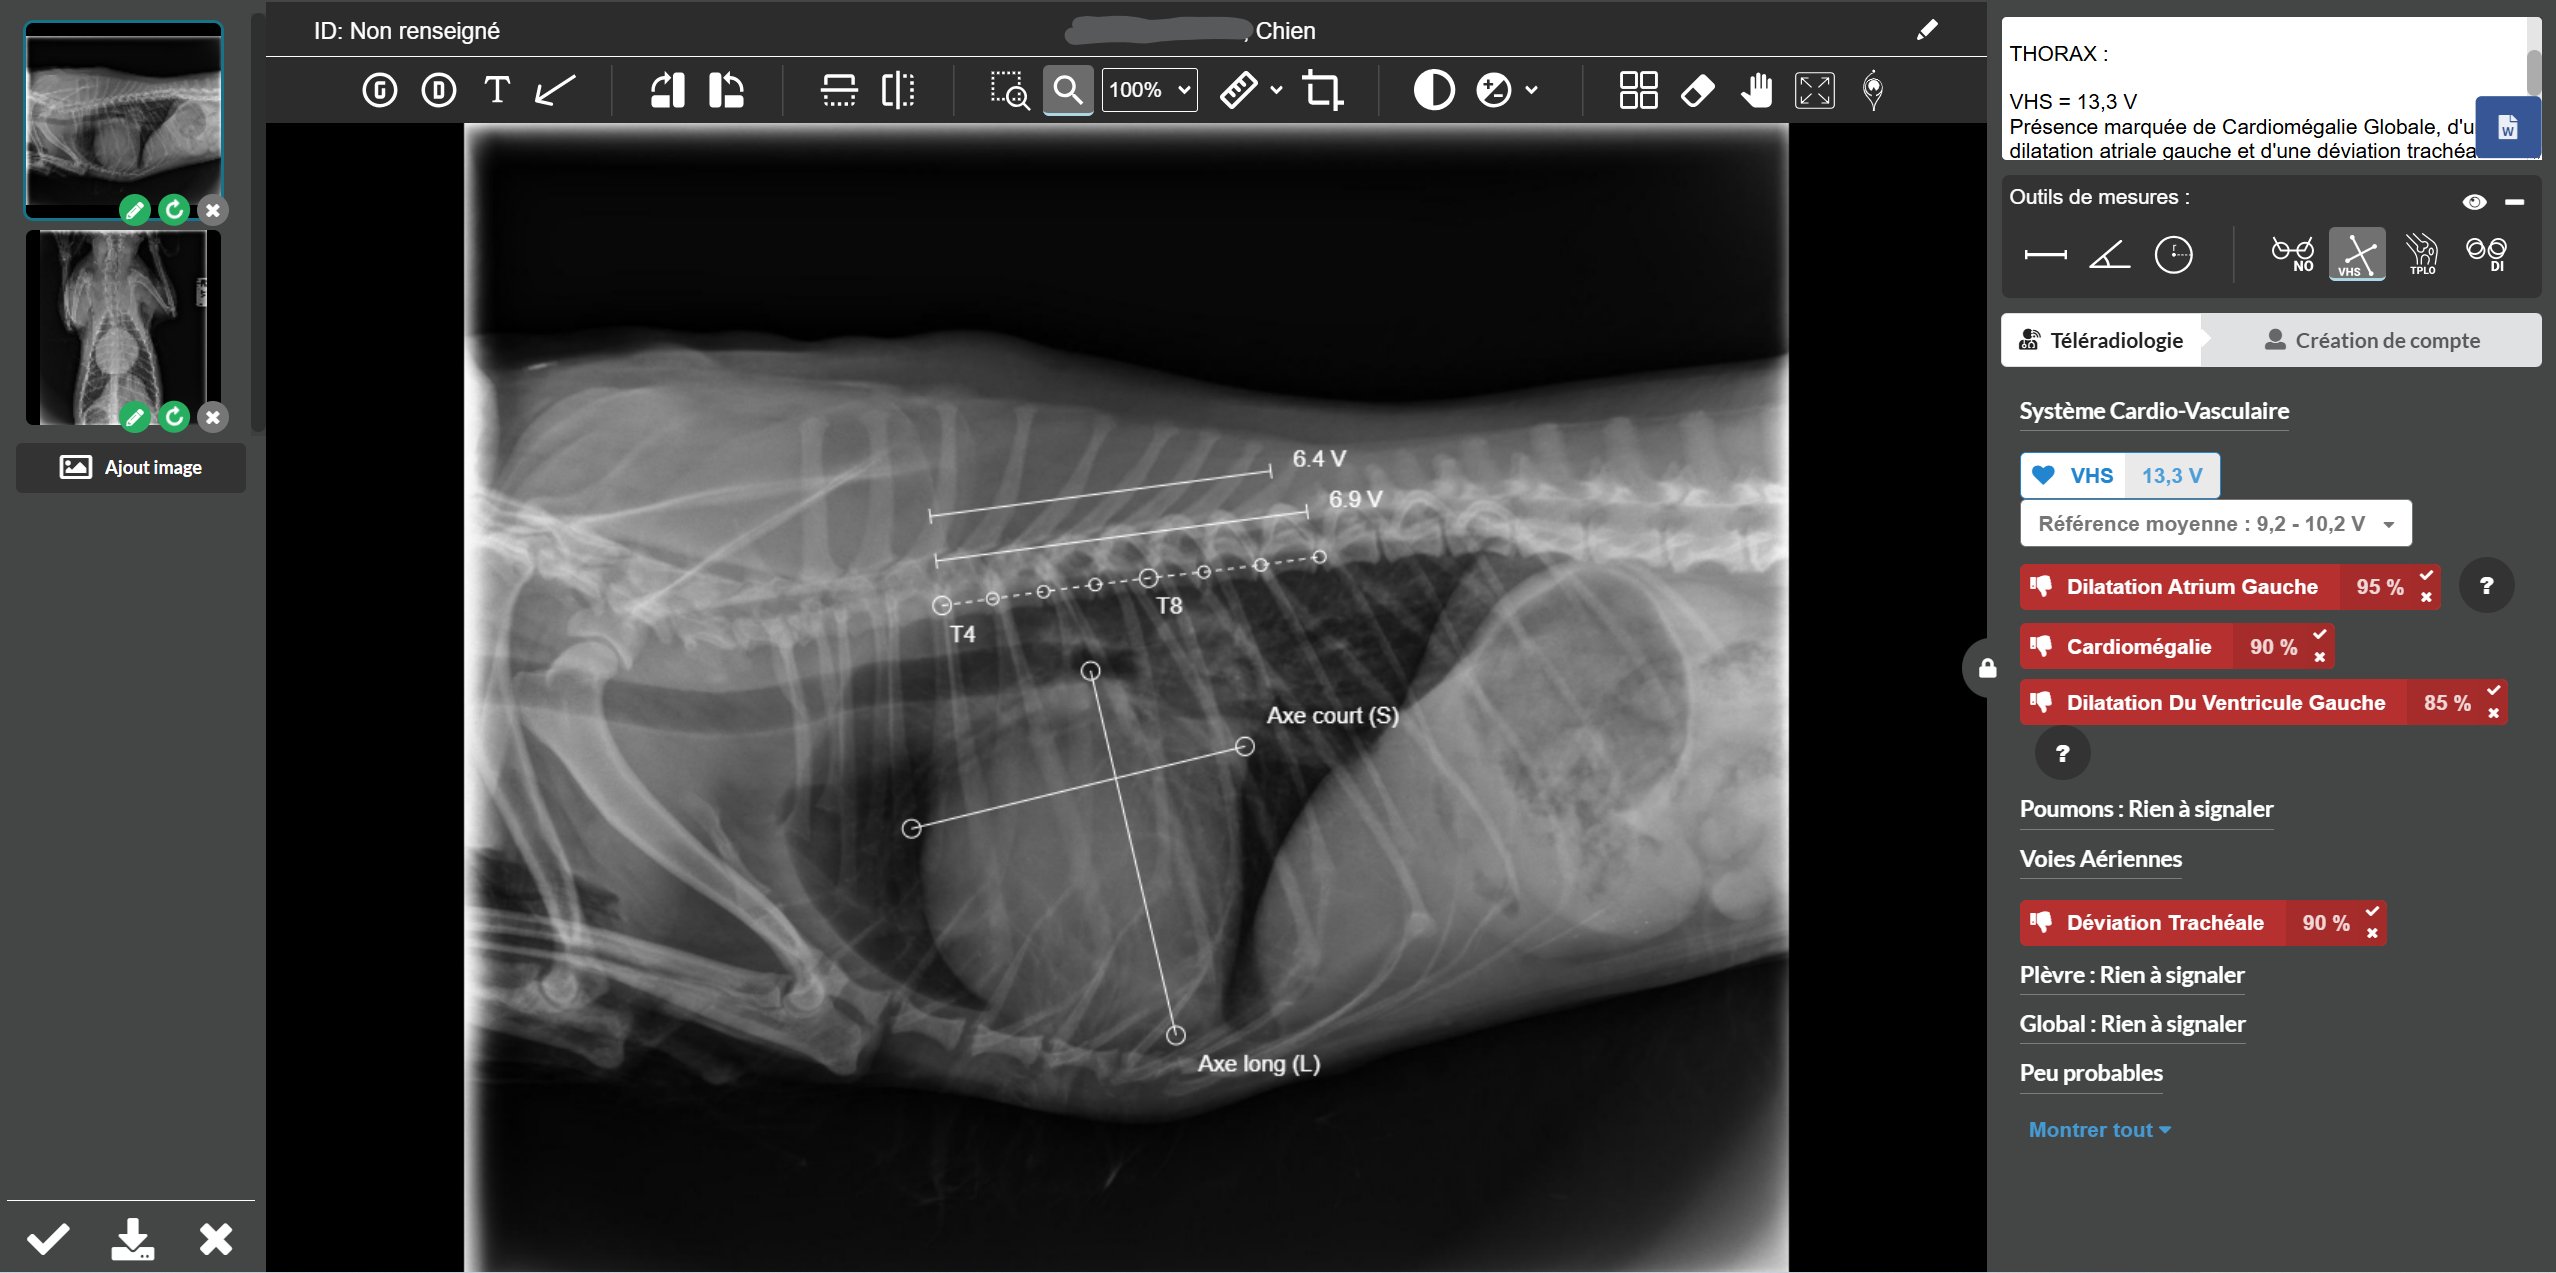

Exemple de mesure automatique du VHS par Picoxia.

- 16 types de lésions thoraciques et la mesure automatique du VHS ;